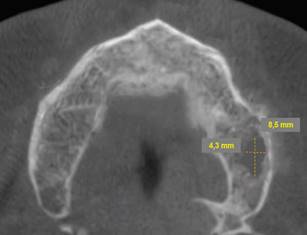

Periapical radiographs were initially ordered. They showed a loss of continuity of the bony trabeculae with irregular, faint osteolytic areas without root debris or foreign bodies (Fig.4 A, B). A CBCT of the maxilla was ordered to evaluate the extent of the lesion. The CBCT showed a radiolucent and osteolytic area at the maxillary bone tissue, measuring 8.5 mm x 5.4 mm, with irregular, poorly defined borders, and which did not involve the buccal, palatine, or maxillary sinus cortical areas (Fig. 5). Microscopic study of the necrotic tissue debris confirmed areas of bone tissue necrosis with inflammatory infiltrate, confirming the MRONJ diagnosis.

Cross-section showing an osteolytic area on the left side of the maxilla measuring 8.5 mm x 4.3 mm is observed.

Given the patient’s systemic and local history, conservative management was performed after the patient signed an informed consent. Twice-a-day rinsing with 0.12% chlorhexidine was prescribed for 14 days, as well as pentoxifylline 400 mg tablets every 12 hours and tocopherol 1000 IU, 1 tablet every 24 hours. Antibiotic treatment with amoxicillin/clavulanic acid (875/125 mg) was also indicated for 14 days to treat the co-occurring infection. The patient was monitored after 14 days. We observed a decrease in purulent content and inflammation, with persisting communication with bone tissue. Antibiotic treatment was discontinued after one month. The rest of the treatment remained unchanged (PENTO protocol + topical antiseptics). The patient would be monitored every two weeks. The clinical behavior of the lesion was evaluated every two weeks. The lesion was cleaned and irrigated with topical antiseptic 0.12% chlorhexidine. The patient reported improved symptoms after six months. He reported decreased pain and bleeding in the affected area. There was evidence of healing of the affected mucosa, continuity disruption, absence of bleeding, and no inflammation of the surrounding tissue (Fig. 6). A control CBCT was ordered, which showed bone neoformation, no radiolucent areas, and bone tissue without alterations (Fig. 7). The patient continued to be monitored for two months, with no clinical or radiographic signs of MRONJ recurrence.

Bone neoformation and recovery of bone trabeculation with regression of radiolucent areas.